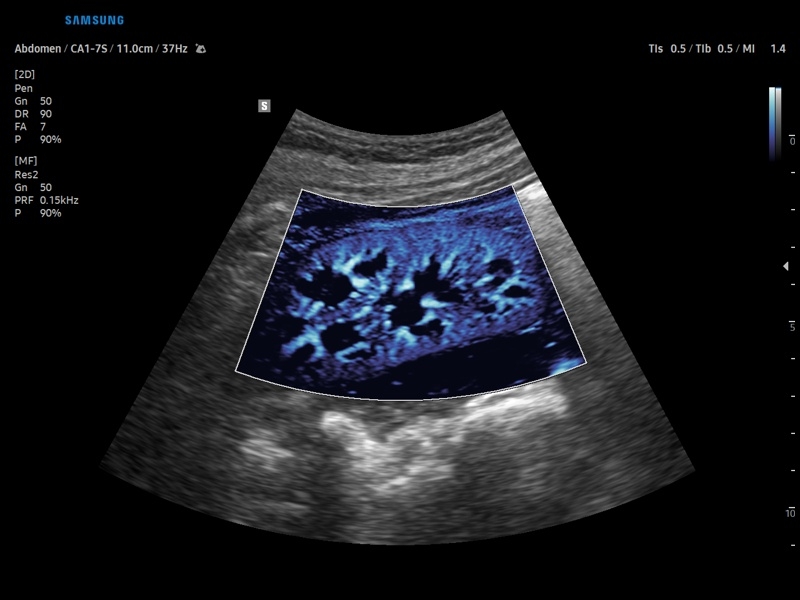

• Контрастное усиление CEUS+

• Технологии визуализации: MV Flow, LumiFlow, SEE Stream, Panoramic

• Модуль CEUS+ (Contrast Enchansment UltraSound) - программа, позволяющая проводить обследование с применением контрастных агентов.

• Модуль MV-Flow – программа (режим), позволяющая визуализировать кровоток в микроциркуляторном русле с высоким разрешением без использования контраста.

• Модуль LumiFlow – программа отображения кровотока с объемной графикой для лучшего понимания архитектоники сосудистого русла.

• Программа SEE Stream – режим недопплеровской визуализации кровотока в реальном масштабе времени.